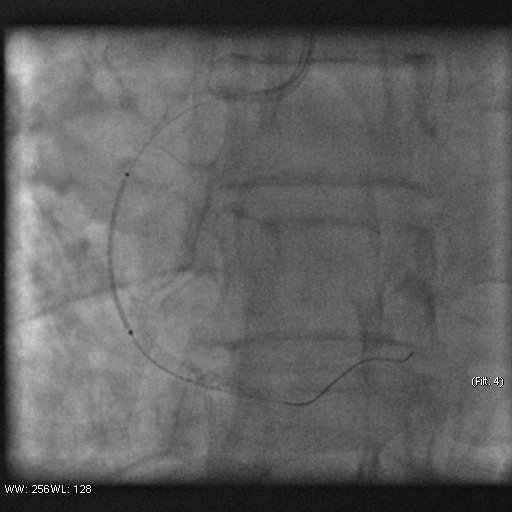

Stenosis of the anterior interventricular artery in the 6.7 segment is 95%. Stenosis of the orifice of the diagonal artery of the 1st order is 95%. Stenosis of the circumflex artery in the 13th segment is 40%. During coronary angiography, pronounced spasm is noted in the 2nd segment of the right coronary artery with complete occlusion of the artery lumen. After stopping the spasm, coronary angiography shows a spiral (spontaneous) dissection of the right coronary artery from segments 1 to 3.

A guiding catheter JR 3.5 6Fr was inserted along a 0.035" 260.0 cm guidewire. The guidewire was removed. The right coronary artery was catheterized. A 7Fr Y-click connector (complete with an insertion device and a guidewire rotation device) was connected to the guiding catheter. A coronary guidewire Whisper ES 0.014" 190 cm, Asahi Gaia Third 0.014" 190 cm was inserted and brought into the orifice of the right coronary artery. The guidewire was inserted beyond the lesion zone of the right coronary artery in segment 2, then into the distal sections. Wilma NC 2.00*20.0 mm and Wilma NC 3.00*15.0 mm balloon catheters were inserted alternately along the coronary guidewire - predilation of the lesion zone of the right coronary artery in segment 2 was performed. Inflation of balloon catheters 14 atm. with an inflator, the balloon catheters are deflated and removed. A stent is inserted along the coronary guidewire - the Yukon Chrom PC 3.0 * 28.0 mm system, Yukon Chrom PC 3.0 * 28.0 mm, Cid Cre 8 3.50 * 25.0 mm, Cid Cre 8 4.0 * 16.0 mm - the stent is implanted in the lesion area of the right coronary artery in the 2nd segment. Inflation of the balloon catheter 9-16 atm. with an inflator, the balloon catheter is deflated and removed. Control coronary angiography - blood flow in the stenting zone is TIMI3, there are no signs of dissection or stent dislocation.